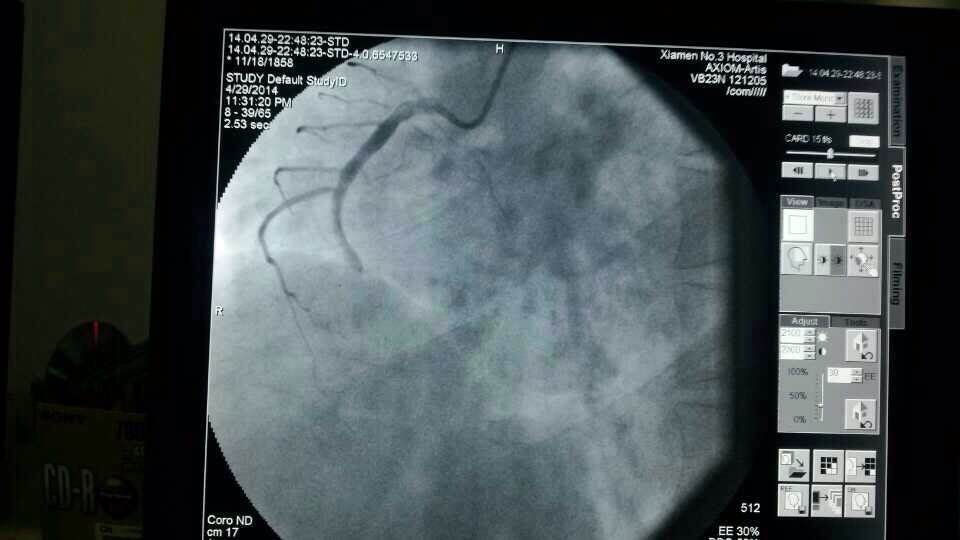

昨天仅一天的时间,厦门第三伦理片 急诊接诊9名胸痛、心梗病人,其中一名河南来厦务工的男性患者,43岁,心脏大面积心梗;另一名翔安心梗患者送到三院时已经心衰终末期,但第三伦理片 马上启动应急机制,心内科抢救技术团队第一时间到位,给予紧急打通血管,植入支架,才保住了两名患者的生命。